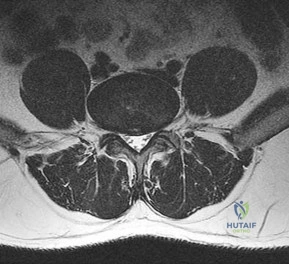

Question 13:

A 65-year-old male presents with neurogenic claudication. He reports pain radiating down both legs when walking, which is relieved by leaning forward on a shopping cart. MRI shows severe spinal stenosis at L4-L5. Which ligament thickens and contributes significantly to the dorsal compression of the thecal sac in this condition?

Correct Answer: Ligamentum flavum

Explanation:

In degenerative lumbar spinal stenosis, hypertrophy and buckling of the ligamentum flavum commonly cause dorsal compression of the thecal sac.